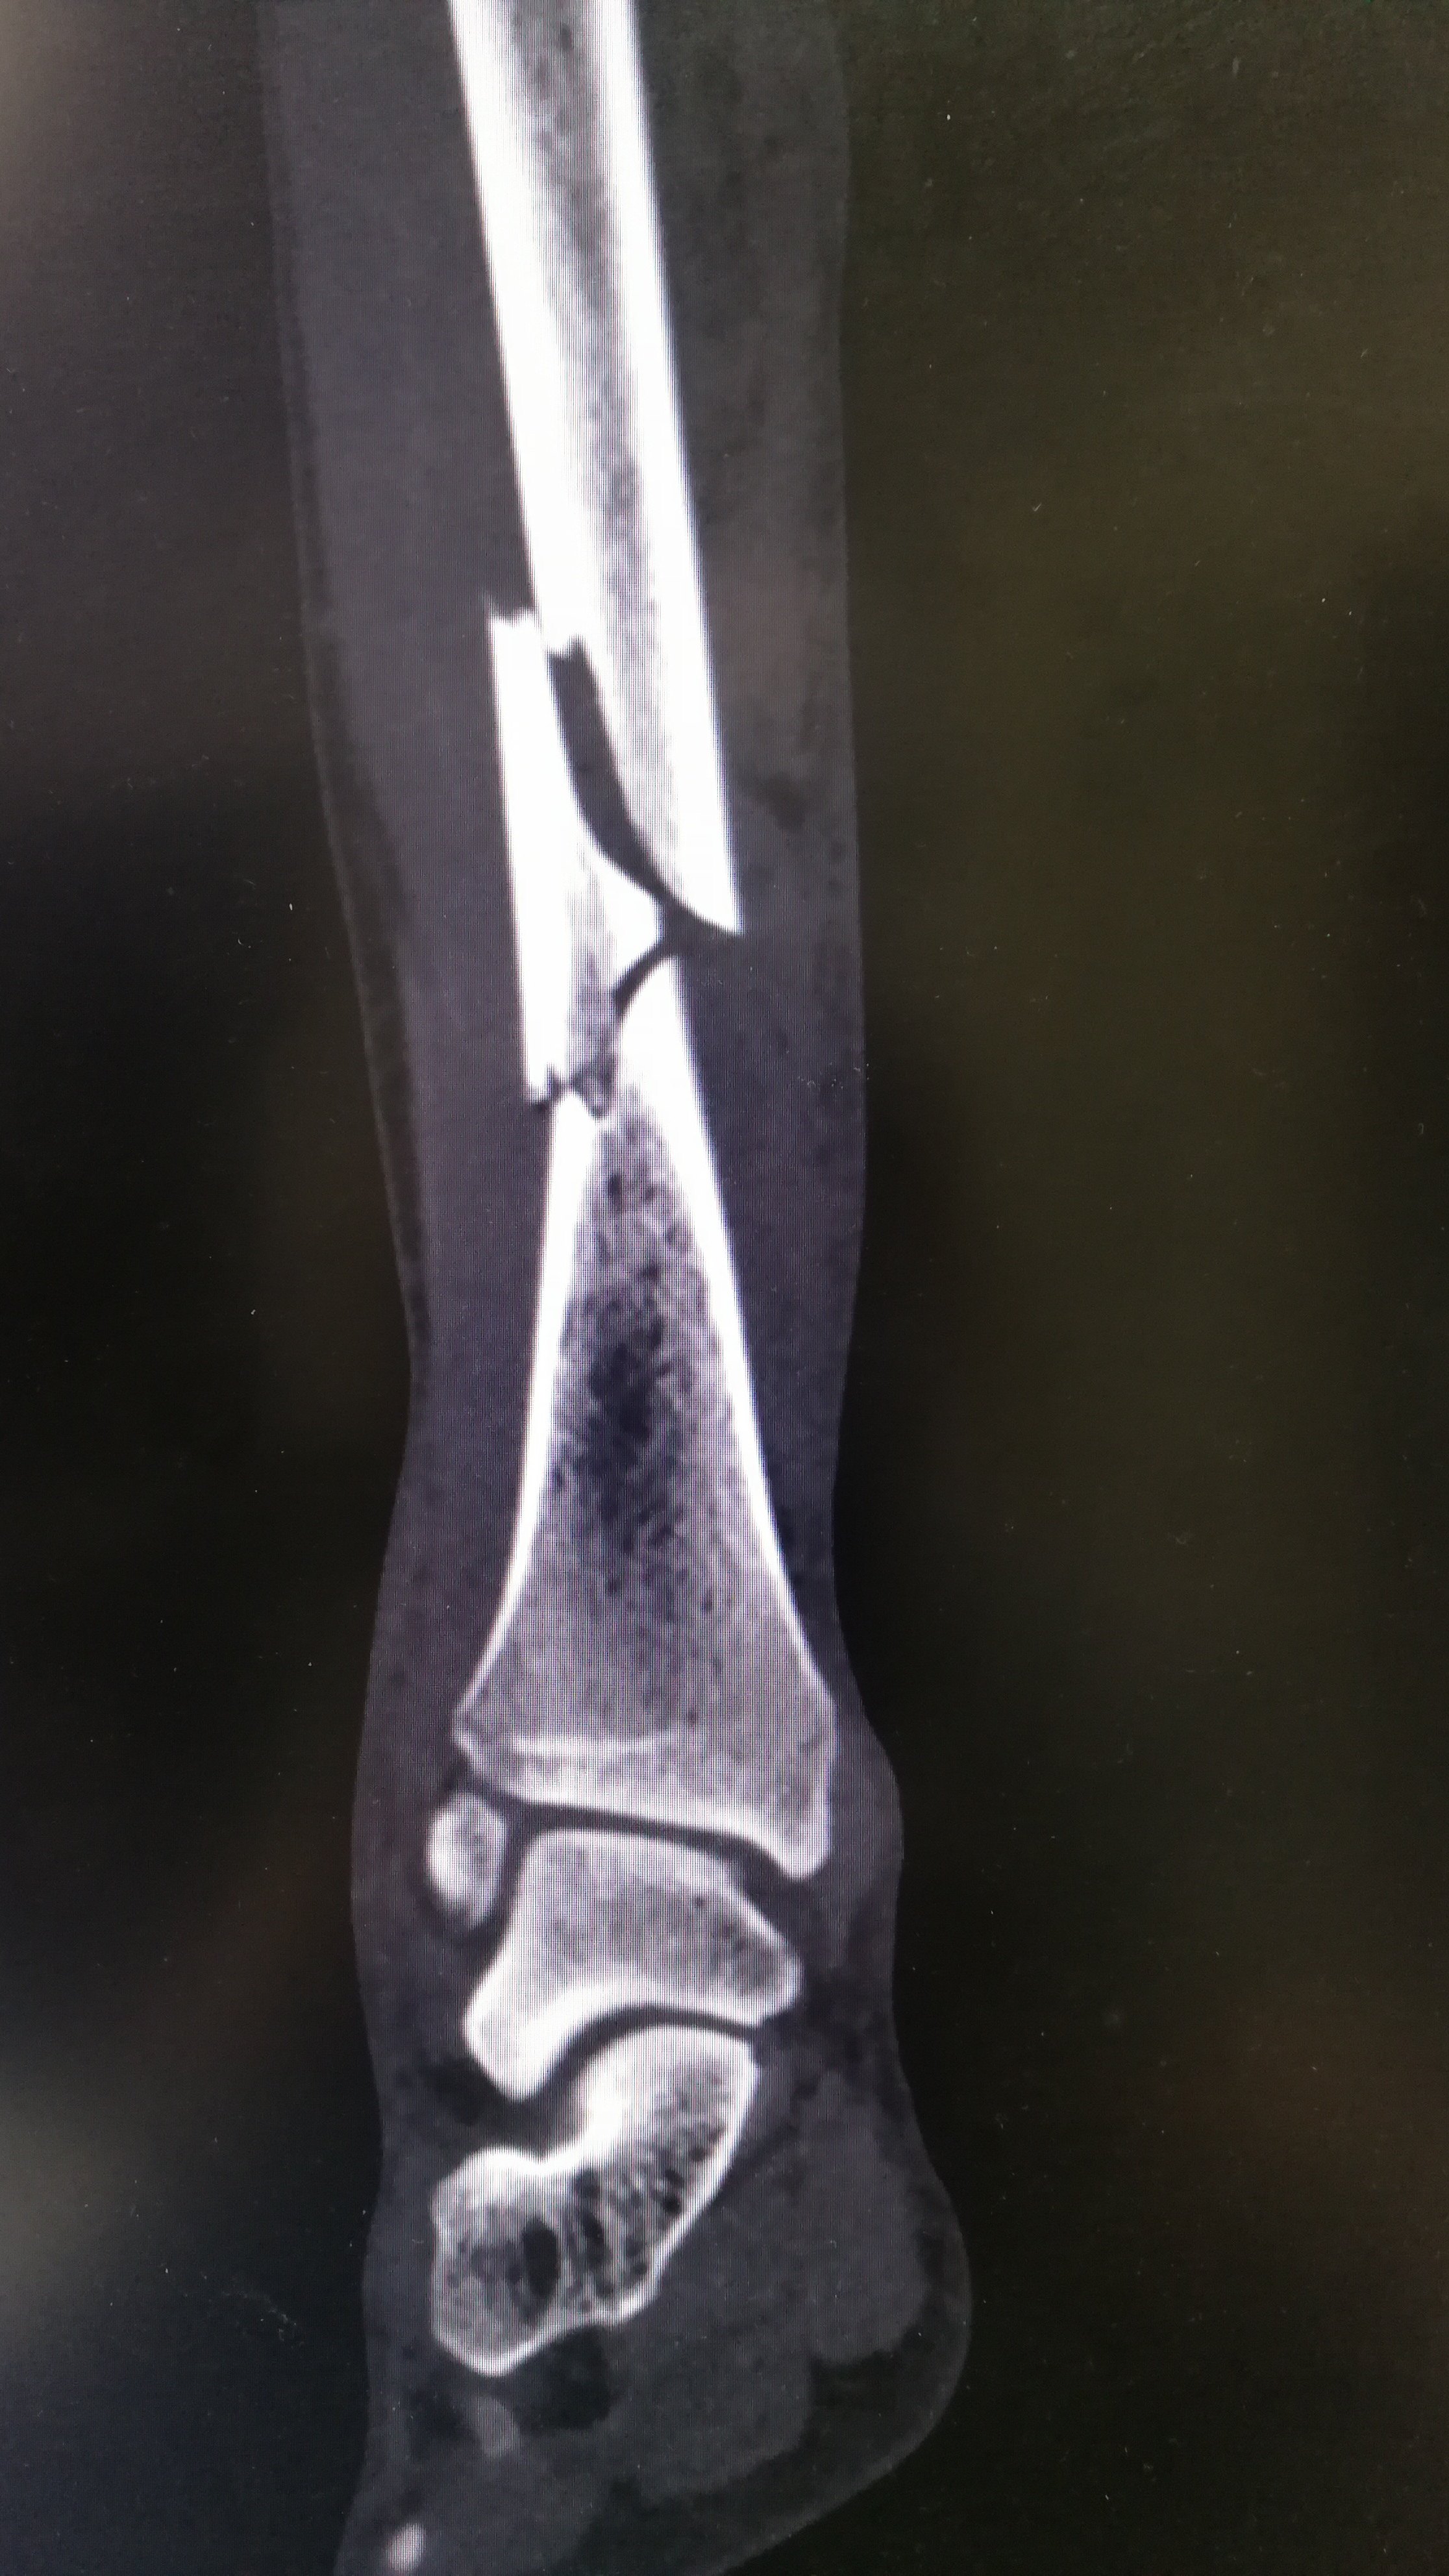

右侧胫腓骨下段骨折

一例严重的胫腓骨远端粉碎骨折

胫腓骨下段骨折闭合复位髓内钉内固定加腓骨下段锁定钢板内固定手术一

pillon骨折:创伤骨科最难治的骨折之一!惟有心灵手巧,方得水到渠成!